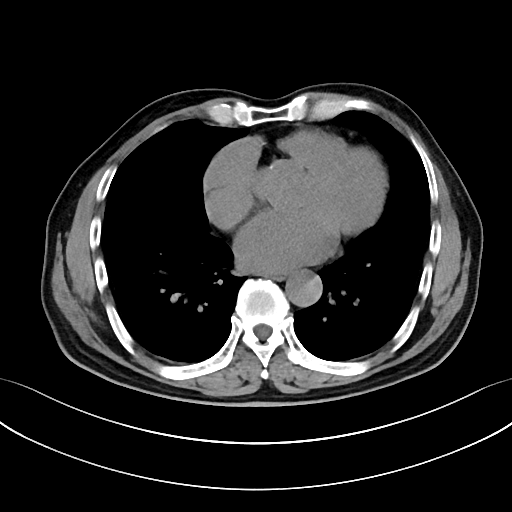

如何通过cta判断急性/慢性主动脉夹层?